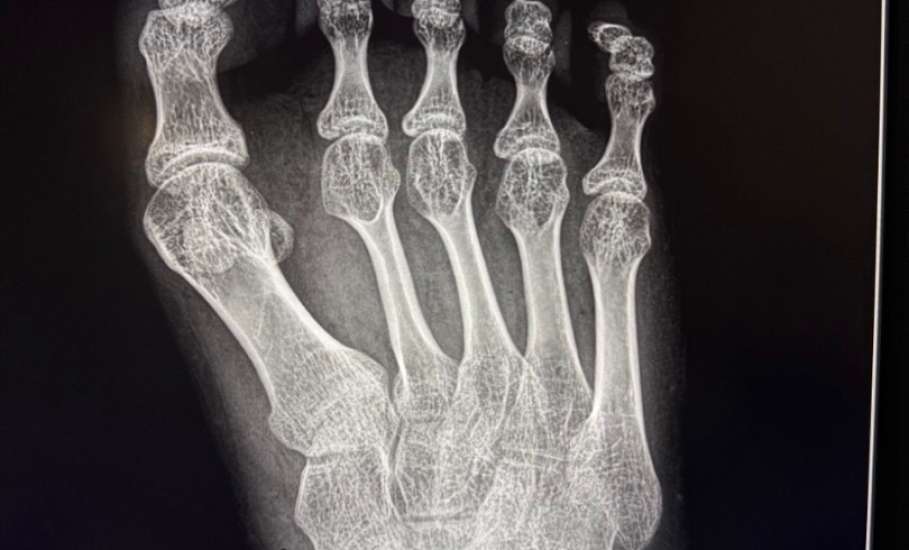

• В Елецкой детской больнице проведена сложная операция 17-летней пациентке с детским церебральным параличом

У девушки была приобретенная деформация первого пальца правой стопы 3 степени, вызывавшая боль и затруднения при ходьбе.

Заведующий травматологическим отделением Махач Алиев выполнил реконструктивное вмешательство по методикам Шеде-Брандеса и Арина. Реабилитация проходит успешно.